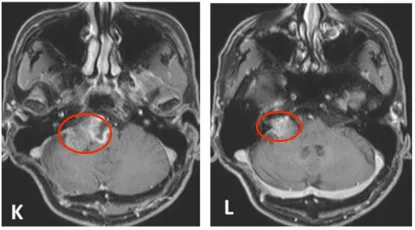

此后长达6年时间,患者坚持每半年进行一次MRI随访,残余肿瘤体积保持稳定。直至2013年11月,常规随访影像显示肿瘤重新出现生长迹象。2014年4月,患者出现进行性头痛、眩晕、恶心等症状,影像学证实肿瘤体积明显增大,并伴有脑干受压表现。

2014年6月,患者接受第三次乙状窦后入路肿瘤切除术。术中所见具有鲜明的双相特征:一部分肿瘤质地柔软,切除相对顺利;另一部分则质地坚韧、富含纤维组织,与面神经、听神经及后组颅神经界限模糊,蛛网膜间隙完全消失。术中在安全范围内尽量切除,仍为次全切除。

术后病理结果彻底推翻了此前的诊断:肿瘤组织呈现出恶性特征,最终确诊为恶性周围神经鞘肿瘤(MPNST),并伴有腺样分化成分。这是前两次病理检查均未发现的恶性转变。